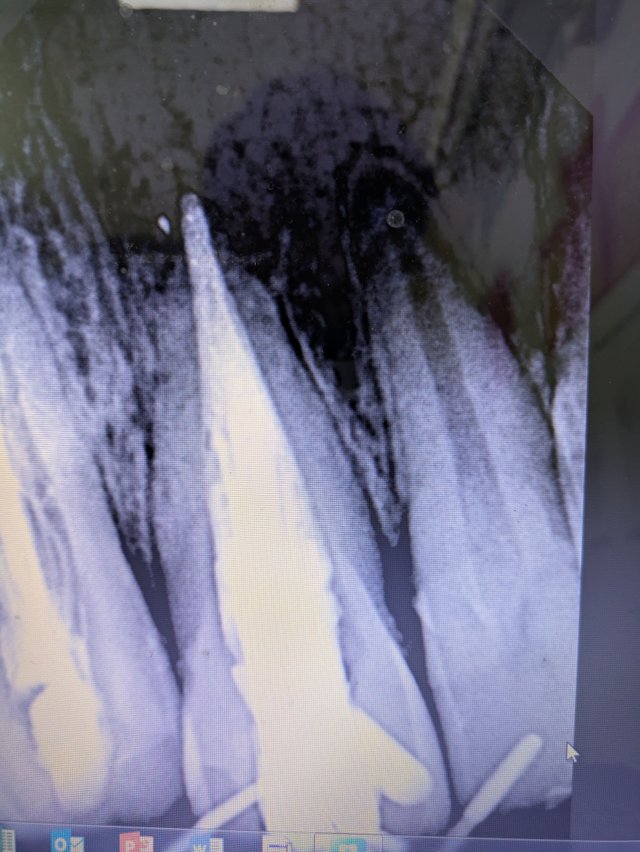

I will not bore you with difficult dental terminology, but just take a look at this image.

I used a material called MTA to help close the immature root. Typically, in such anterior teeth, we use one or two units of a particular substance. But in this case, I had to use nine. Yes, nine. It was the only way to ensure long-term success and stability.